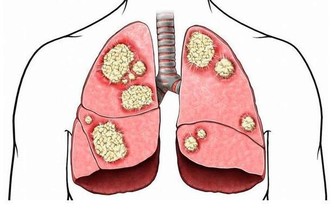

年齡漸長,發生骨質疏鬆的機會也跟著增加。(網絡圖片)

隨著年齡漸長,發生骨質疏鬆的機會也跟著增加,往往一不注意就落入骨質脆弱的環節里。